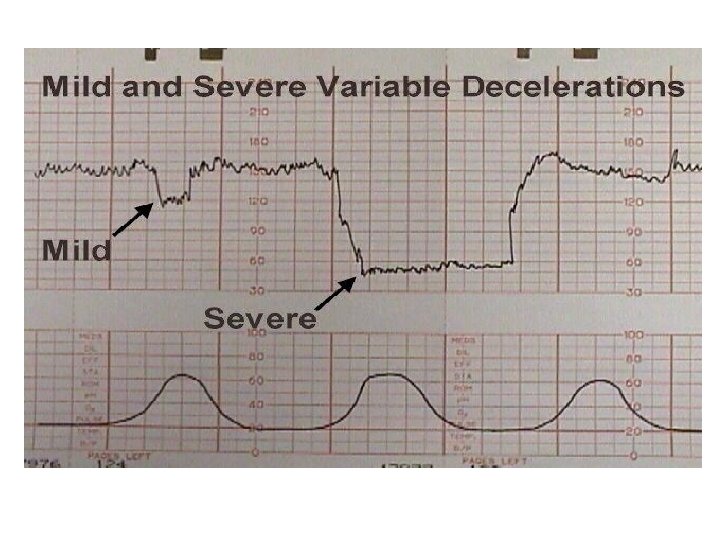

Variable Deceleration Abrupt decrease in FHR of > 15 beats per minute measured from the most recently determined baseline rate. The onset of deceleration to nadir is less than 30 seconds. The deceleration lasts > 15 seconds and less than 2 minutes. A shoulder, if present, is not included as part of the deceleration. Variable decelerations may be observed in up to 50% of NSTs. If nonrecurrent and <30 seconds, they are of no clinical significance.

Variable Deceleration Typical: • shoulders Atypical : • Overshoot • Loss of primary shoulder • Slow return to baseline (late component) • Baseline returns to a lower level(after deceleration) • Biphasic(W shape) • loss of variability during deceleration

Classification severity of variable deceleration • Mild: duration < 30 second or depth up to 80 bpm • Moderate : deceleration < 80 bpm • Severe : deceleration < 70 bpm for more than 60 second